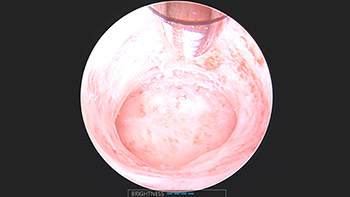

Procedure: Hysteroscopy was done. A submucosal fibroid was identified. Complete resection of the fibroid was achieved with a Truclear resection device.